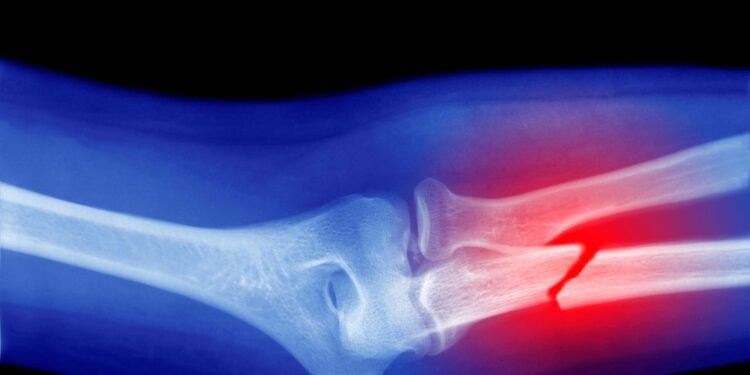

Throughout your life, your bones are replenished. Osteoporosis is a condition where this process goes wrong, with the breakdown of bone outstripping the rate at which it is replaced. This leads to bones weakening over time and becoming more likely to fracture. The condition has many risk factors—age, sex, medications, diet, smoking and drinking, and genetics are all known to influence it—with the disease developing slowly over time. Often people don’t realize they have the condition until they break a bone.

When then looking at animal studies, the researchers found that the accumulation of microplastics in the body decreases the white blood cell count—which is suggestive of alterations in bone marrow function. In addition, these animal studies suggested that the impact of microplastics on osteoclasts may be associated with deterioration of bone microstructure and the formation of irregular structures of cells, increasing the risk of bone fragility, deformities, and fractures.